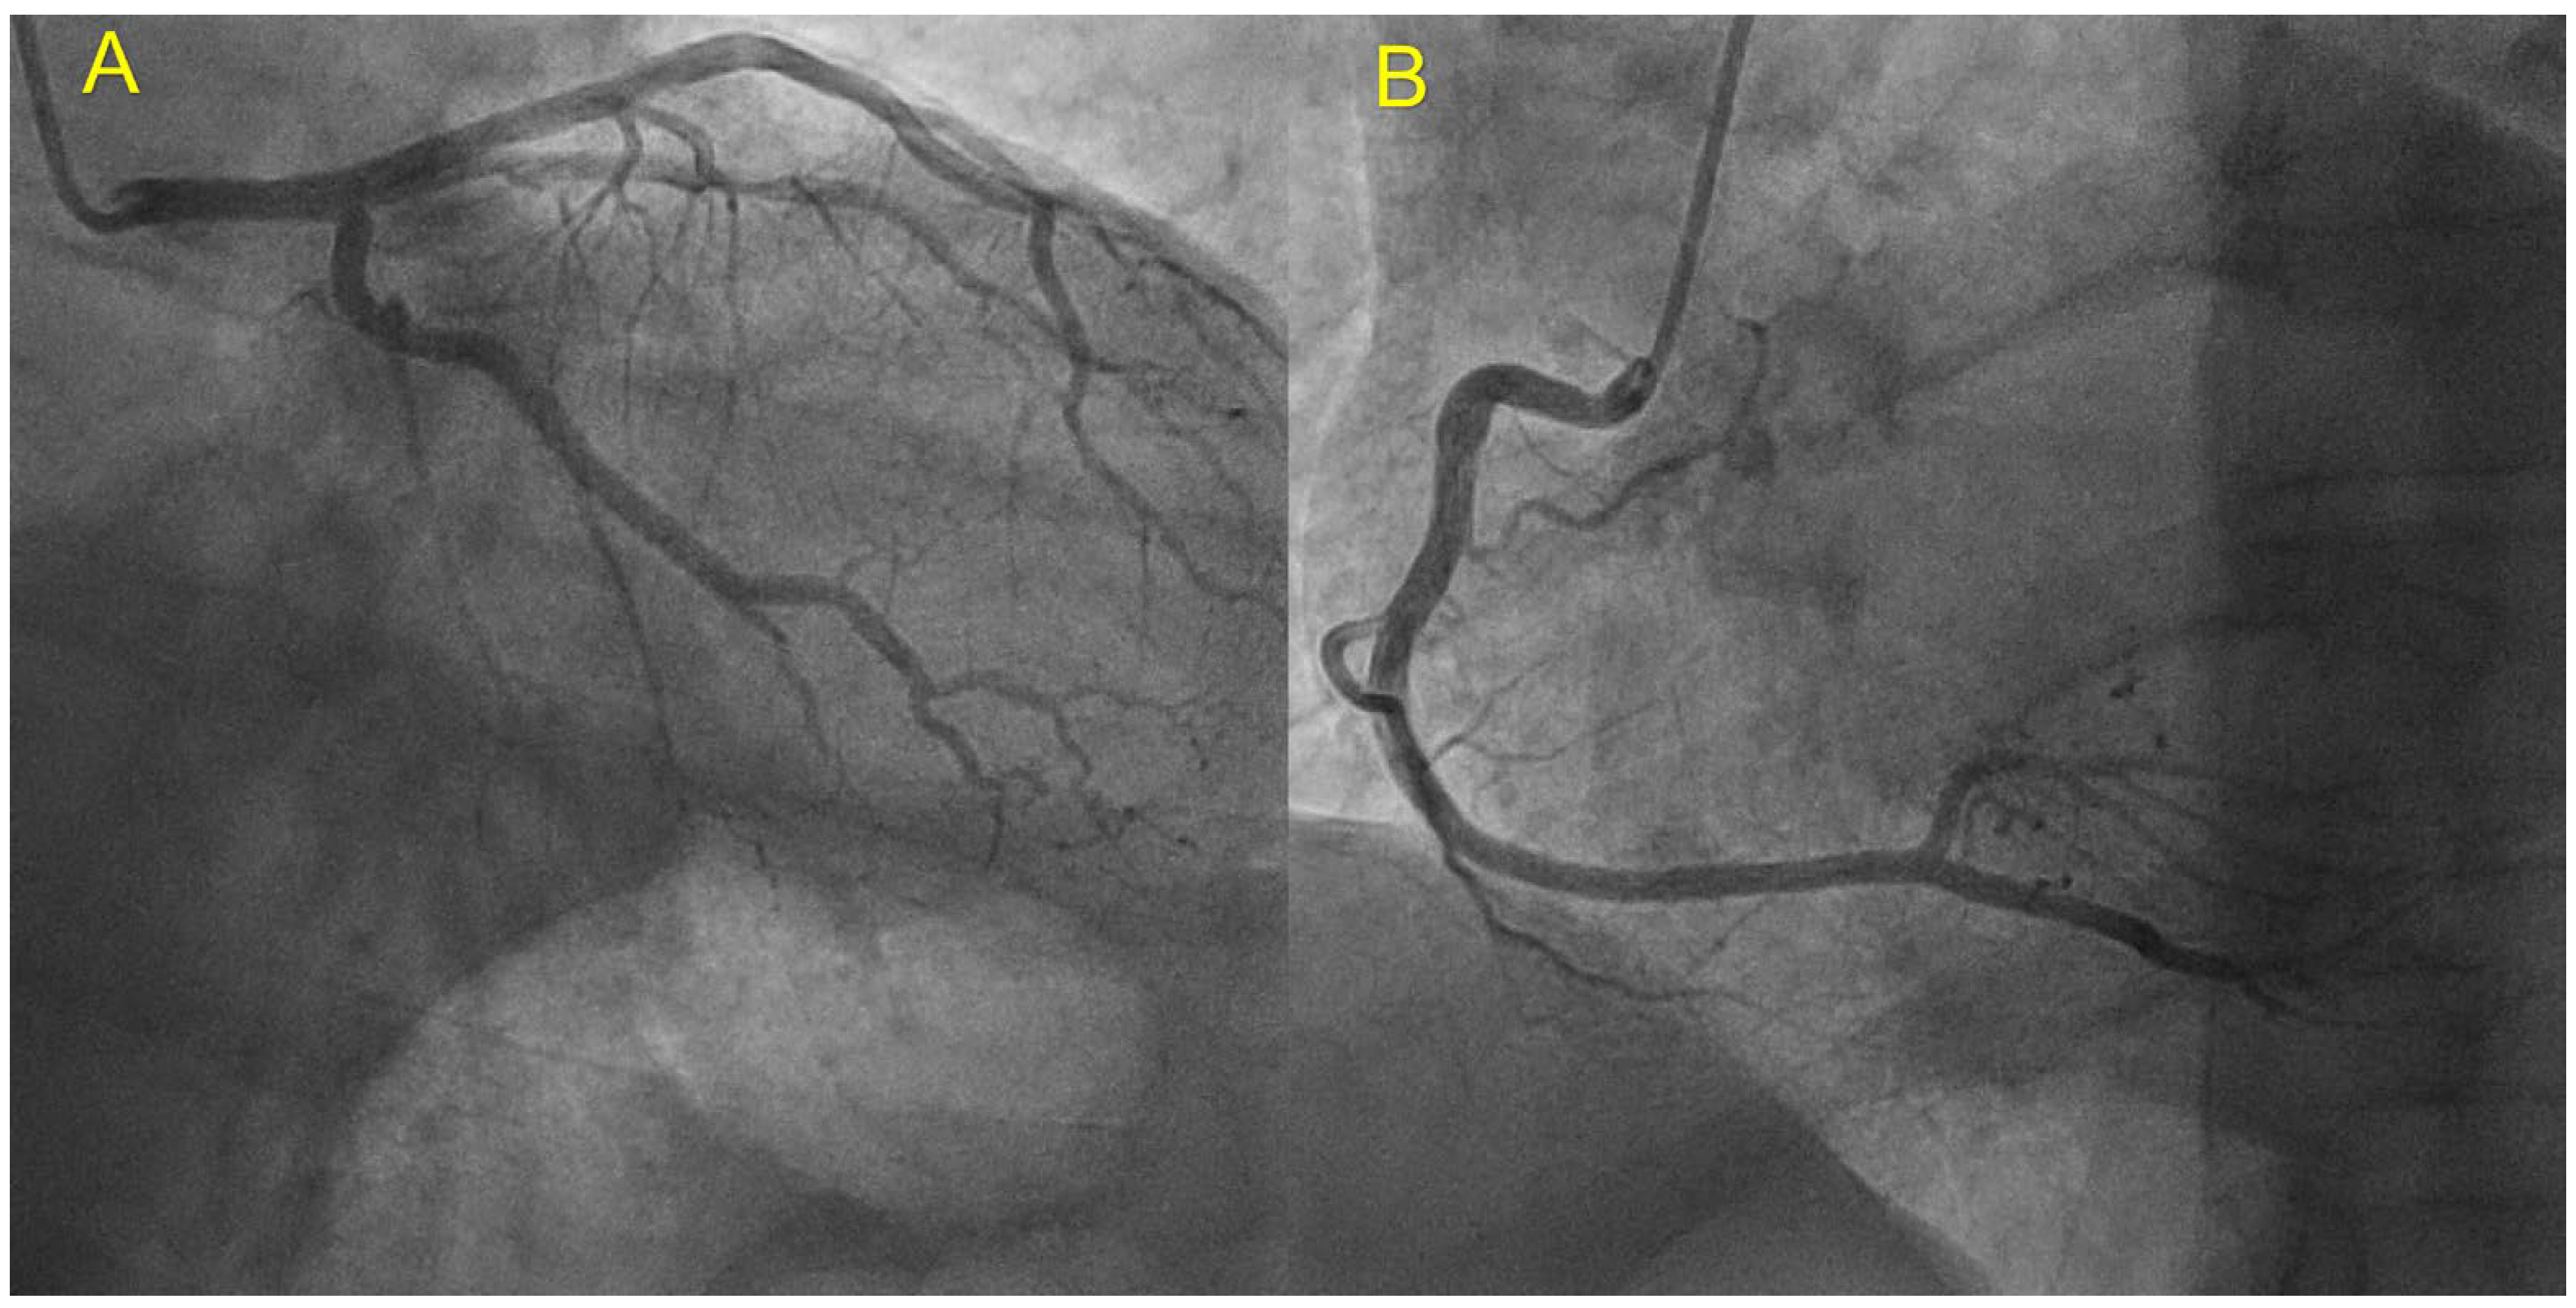

| Coronary angiography | Normal | Normal | Not carried out |